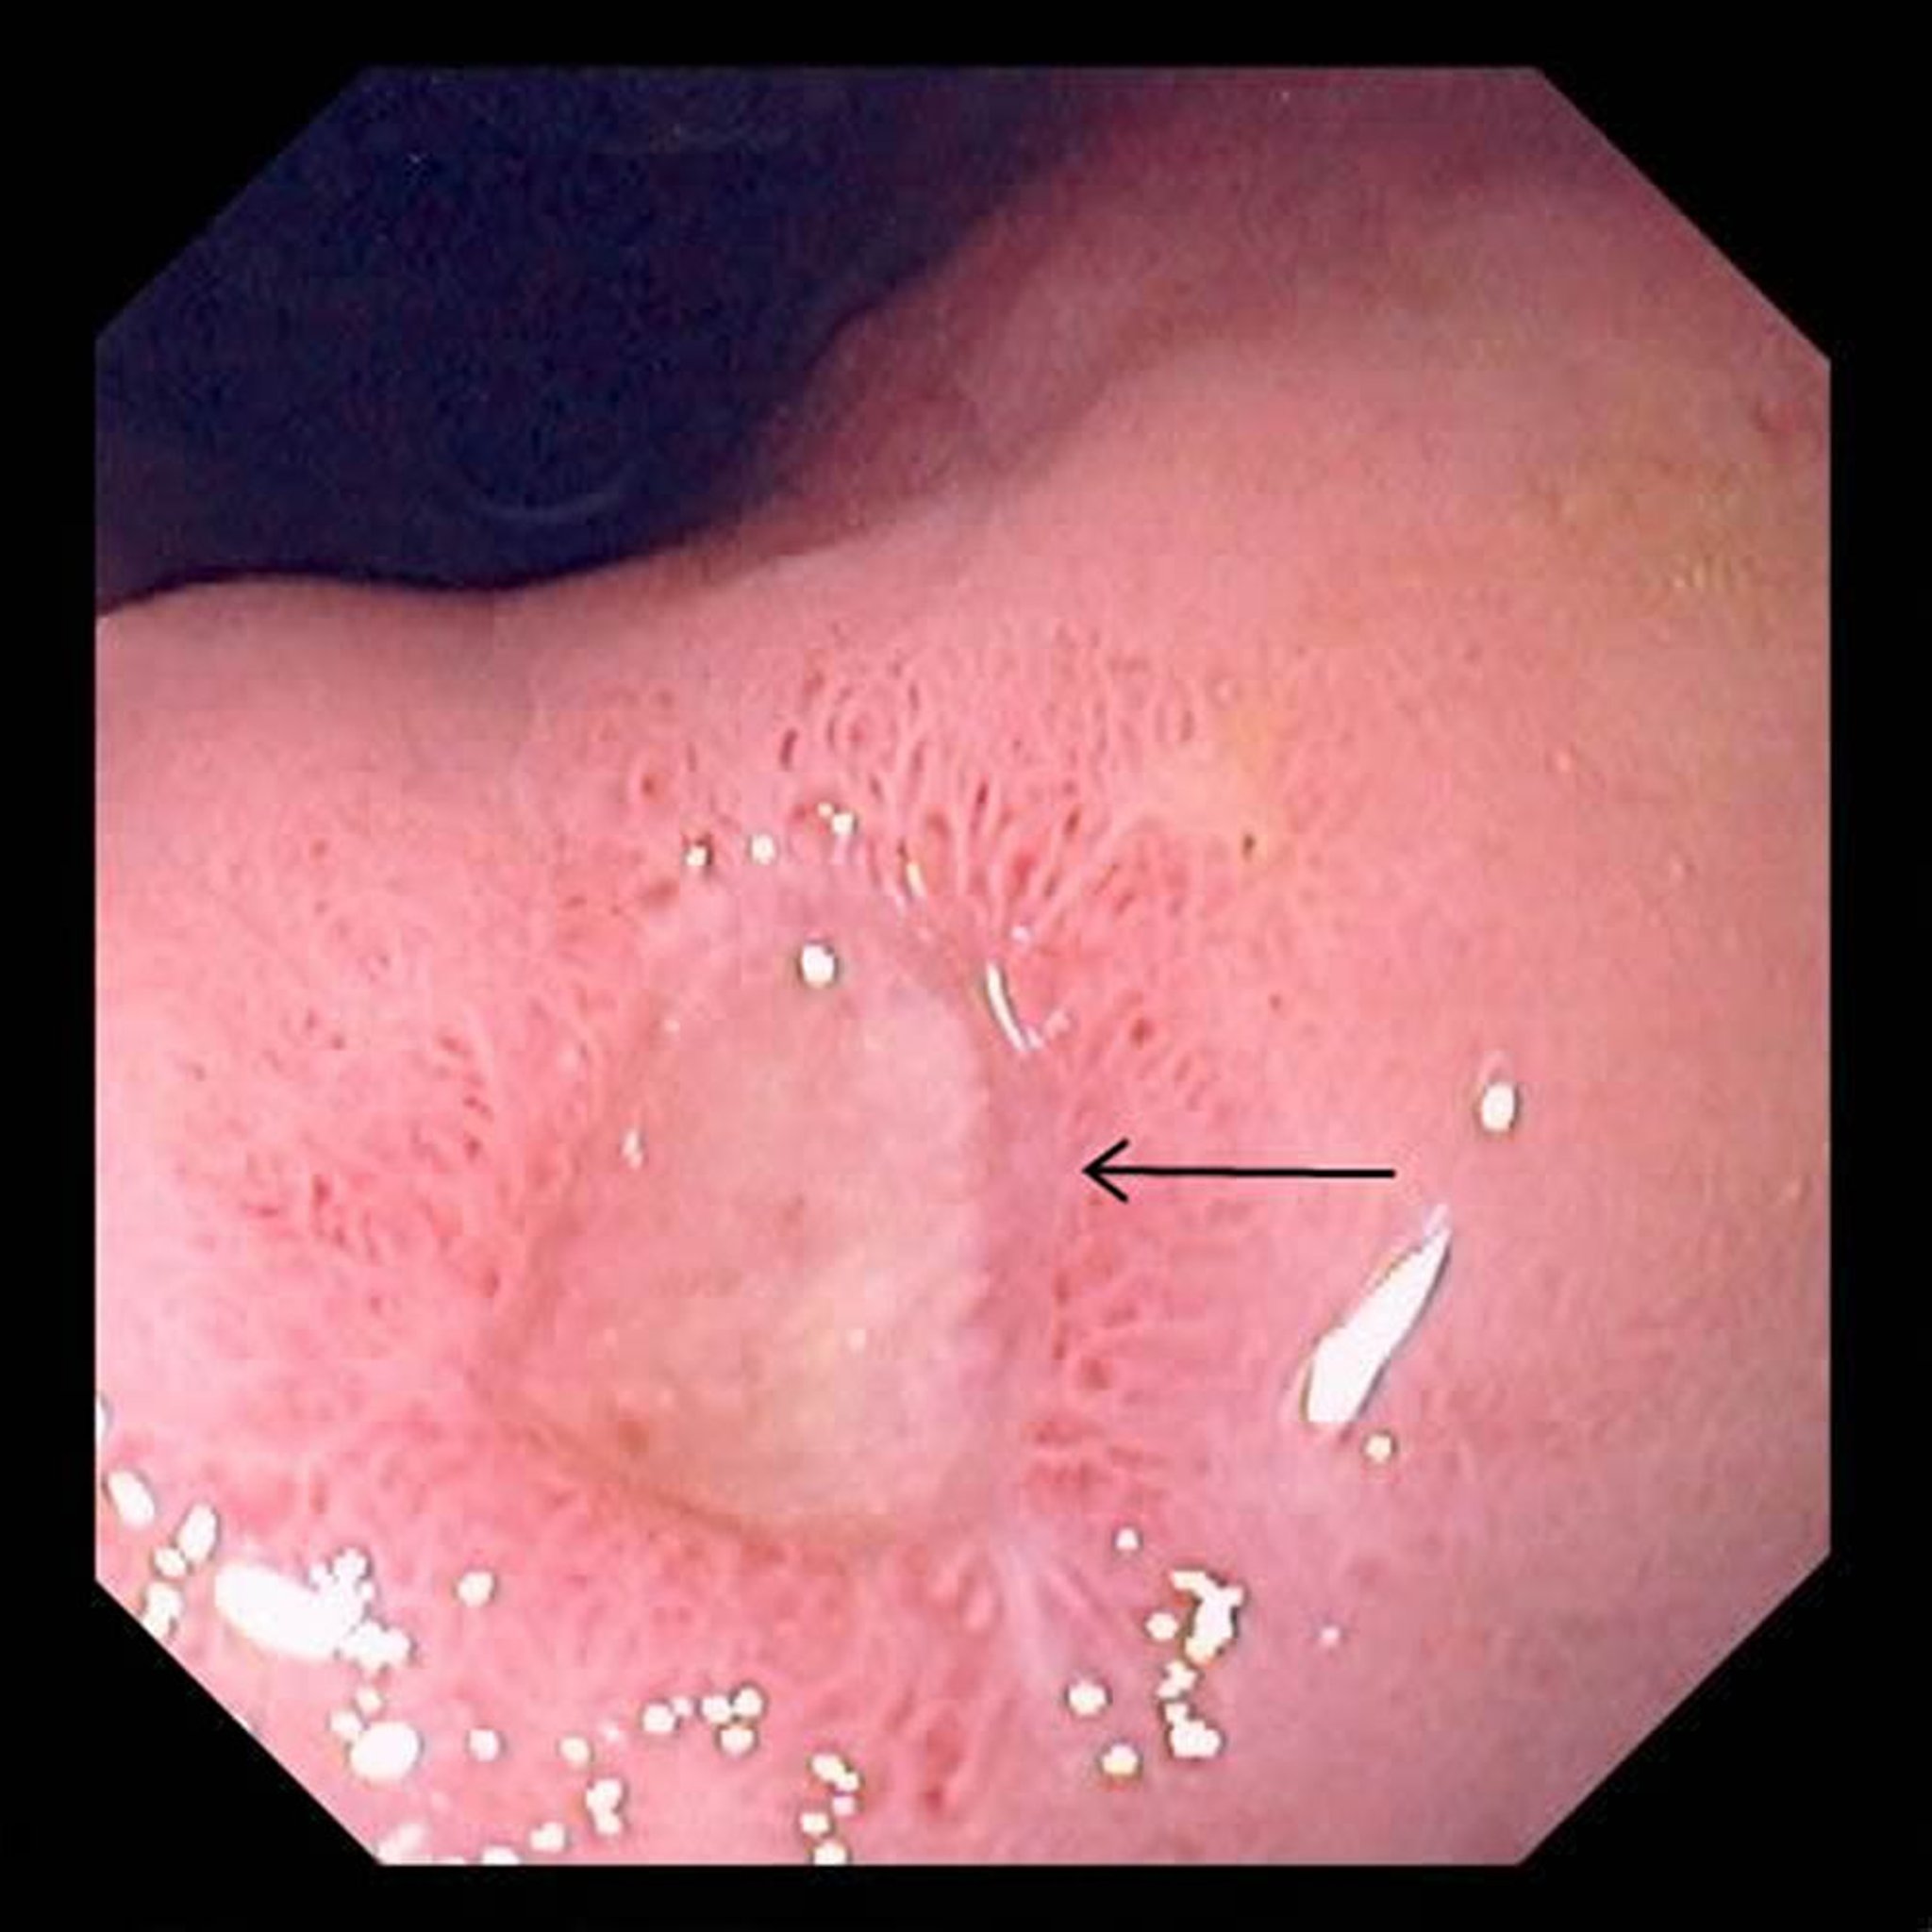

• Endoscopia (passar um tubo de visualização flexível pelo esôfago até o estômago para examinar o estômago)

Durante a endoscopia, o médico costuma colher material para biópsia (uma amostra de tecido para ser examinada sob o microscópio) para tentar detectar a presença da bactéria Helicobacter pylori ou câncer.